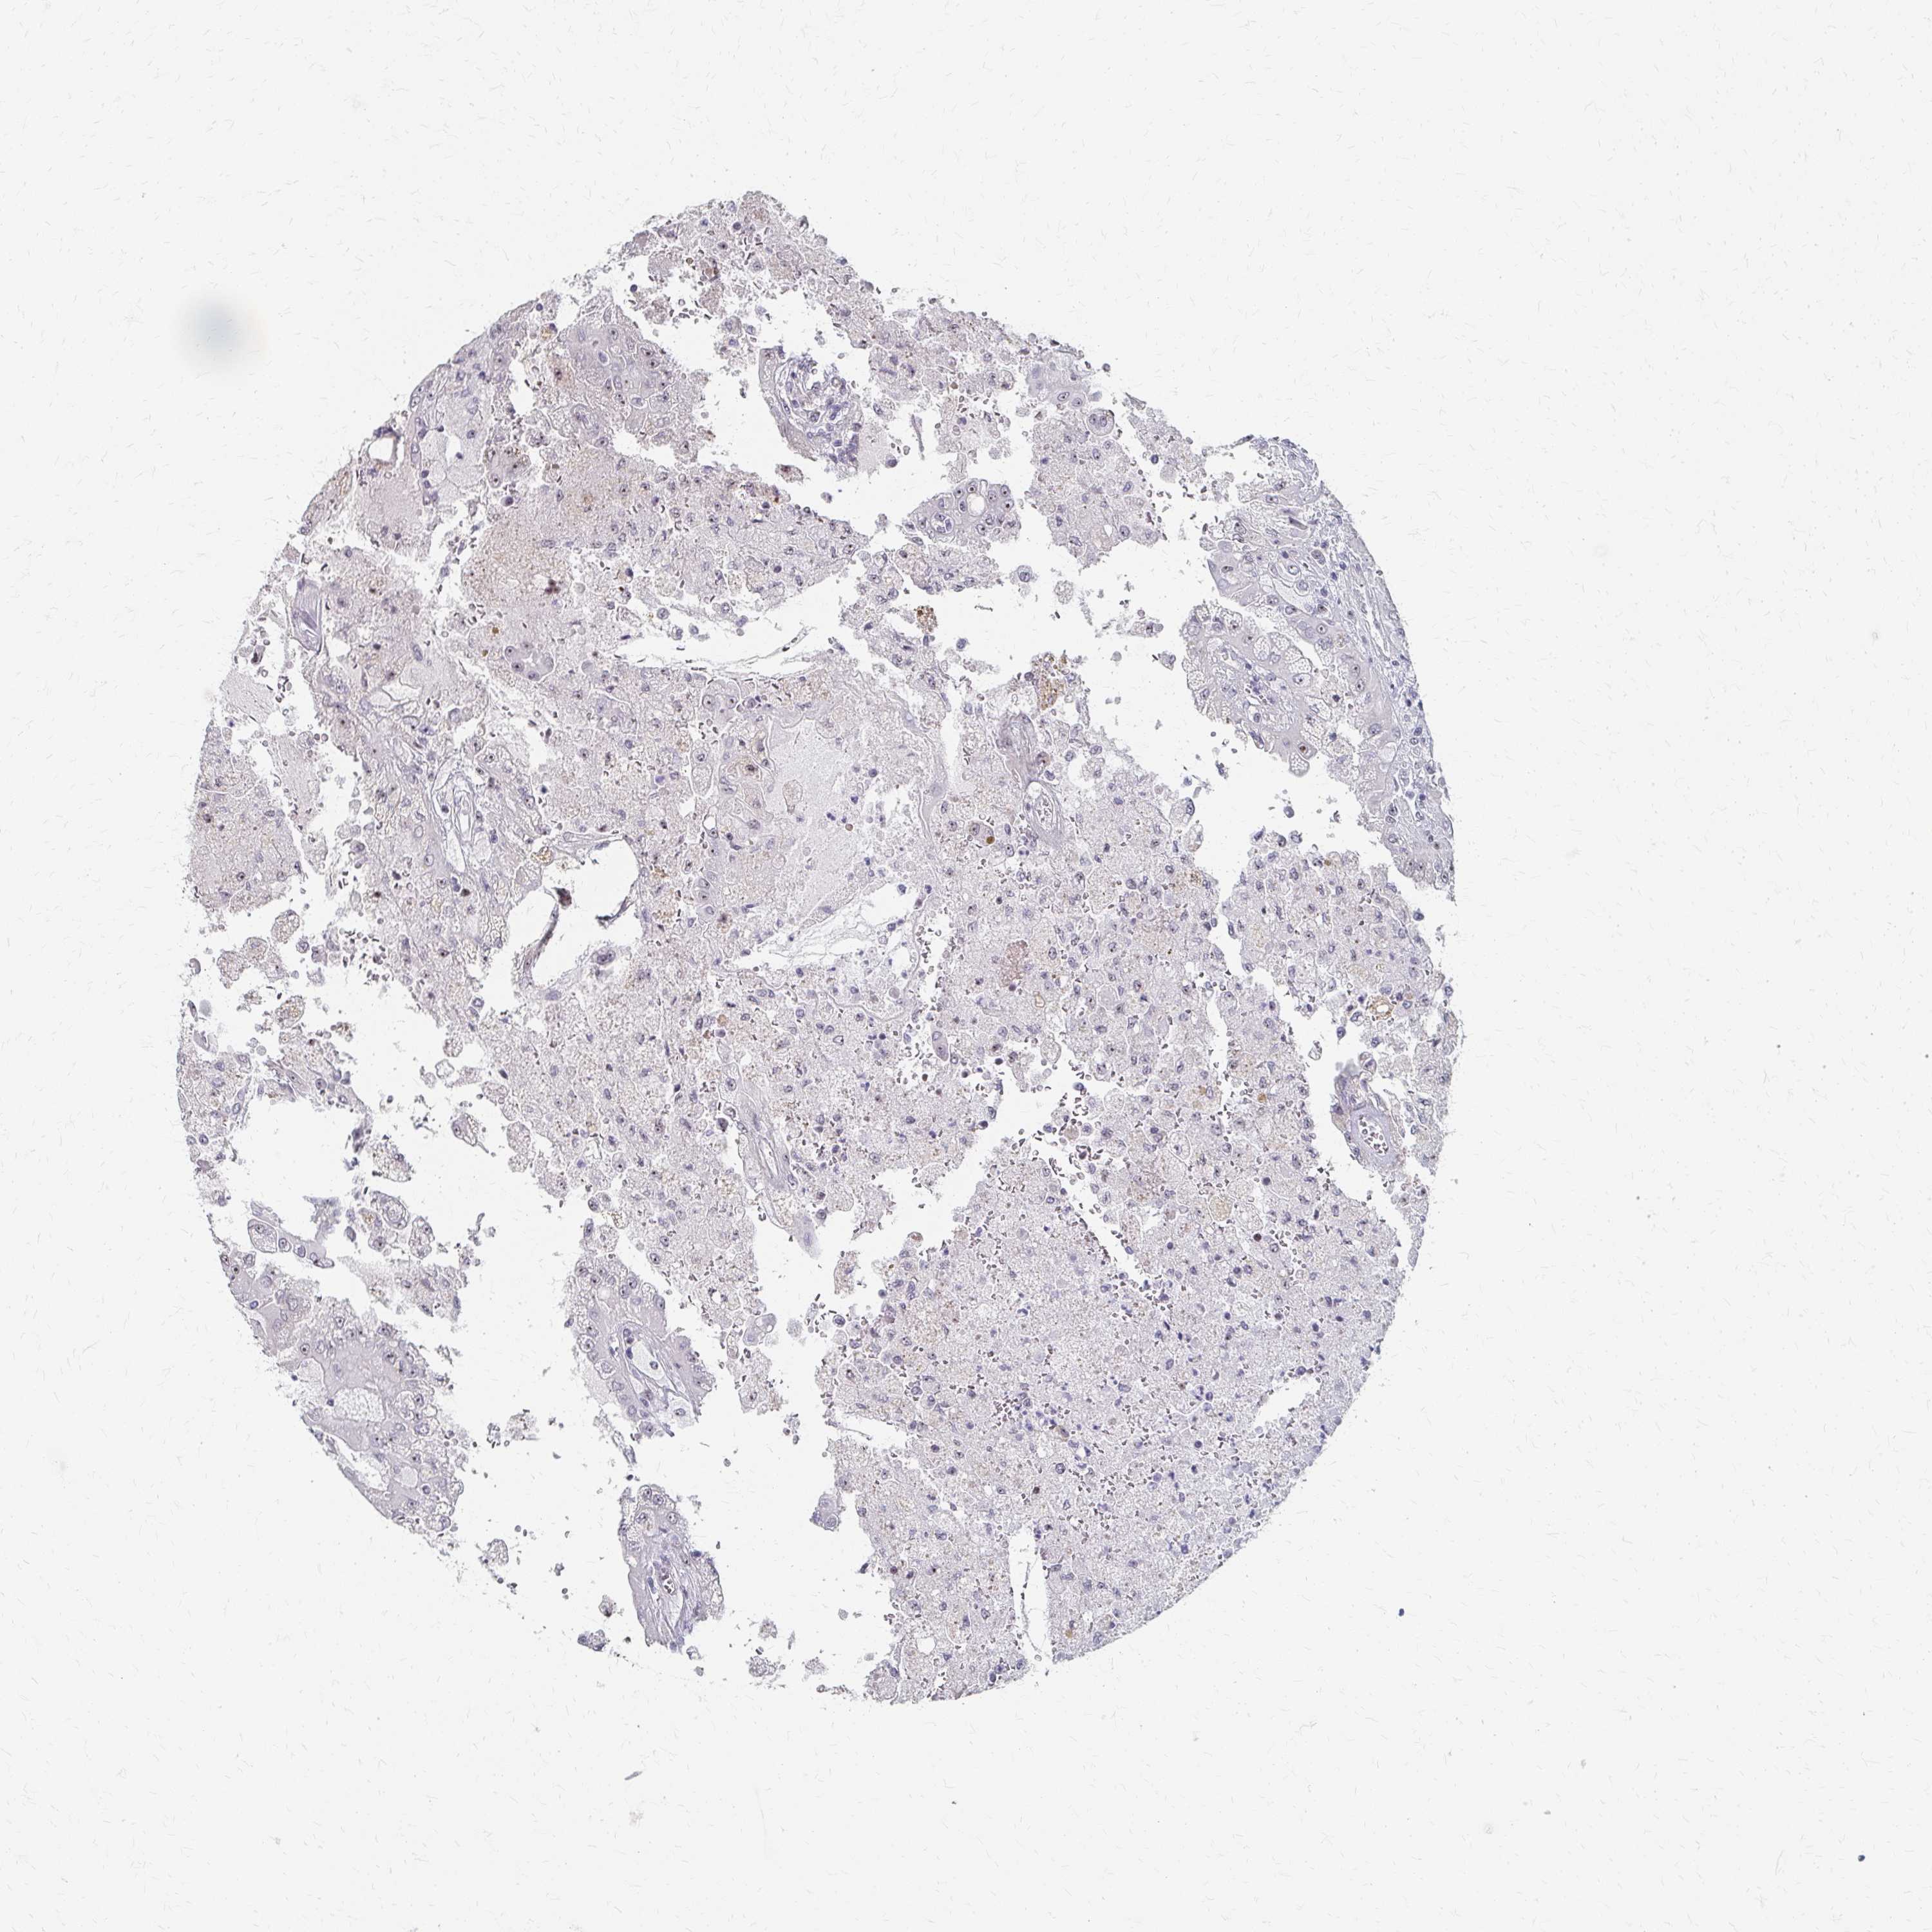

CANCER RENAL CANCER Show tissue menu

Renal cancer

Kidney renal clear cell carcinoma